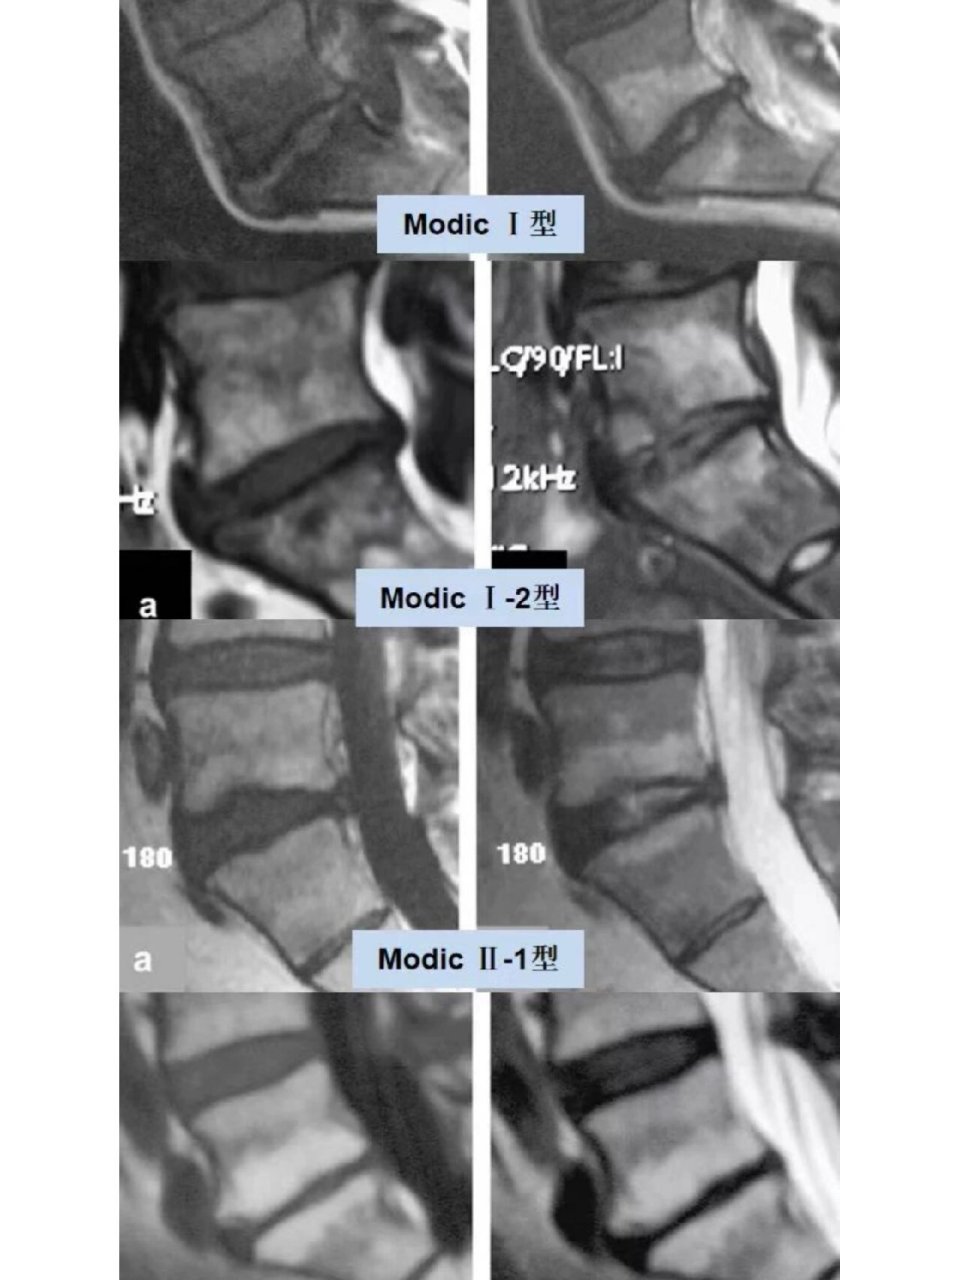

椎体终板炎发生机制分型以及mri表现

椎体终板炎:发生机制,分型以及 mri 表现